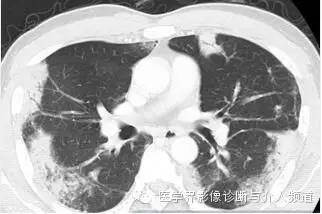

随访胸片

初始胸片示两肺野多灶性斑片影,其中两肺上野靠近外周可见边界欠清的实变影,这是典型的慢性嗜酸性粒细胞性肺炎“肺水肿反转影”的表现。CT示两肺叶多灶性非节段性实变影,病变以两上肺周围性分布为主。

影像学检查在CEP诊断中有重要的作用,CT或HRCT检查能更准确地显示肺内病变的部位,特别是临床怀疑而普通X线胸片表现不典型的病例。

CEP的典型影像学表现:普通X线平片为非节段性、分布广泛互相融合的肺泡及间质性实变,病变以中上肺周围性分布为主,表现为“肺水肿反转影”。CT或HRCT表现为一侧或两侧融合性实变、斑片状实变、磨玻璃影、条带状致密影,实变灶与正常肺组织的分界截然清楚。此种典型征象并非见于所有CEP病例。